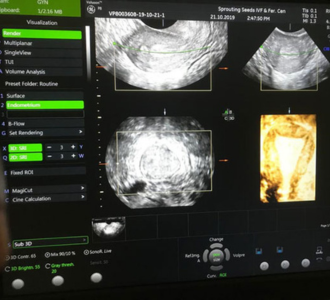

Ultrasonography in Infertility

Ultrasonography forms a key tool in monitoring patients with infertility. It mainly helps in monitoring the growth of the follicle (Egg in the ovary), its rupture and also to monitor the response of the endometrial lining in response to the egg growth and subsequently its release from the ovary. This basic procedure is done by transvaginal sonography(TVS), is a non invasive and cost effective method of determining ovulation. This facility in available at all fertility clinics and at certain sonography institutes and clinics and is called follicular study.

However some women have the fear of transvaginal sonography which is completely baseless. It is mainly psychological and we have seen that most of them get used to it as they proceed in their treatment. This is important because TVS gives more detailed and accurate information as compared to abdominal scan. Also it is many a times needed to do this scan when the women is menstruating and it is perfectly normal to do so.